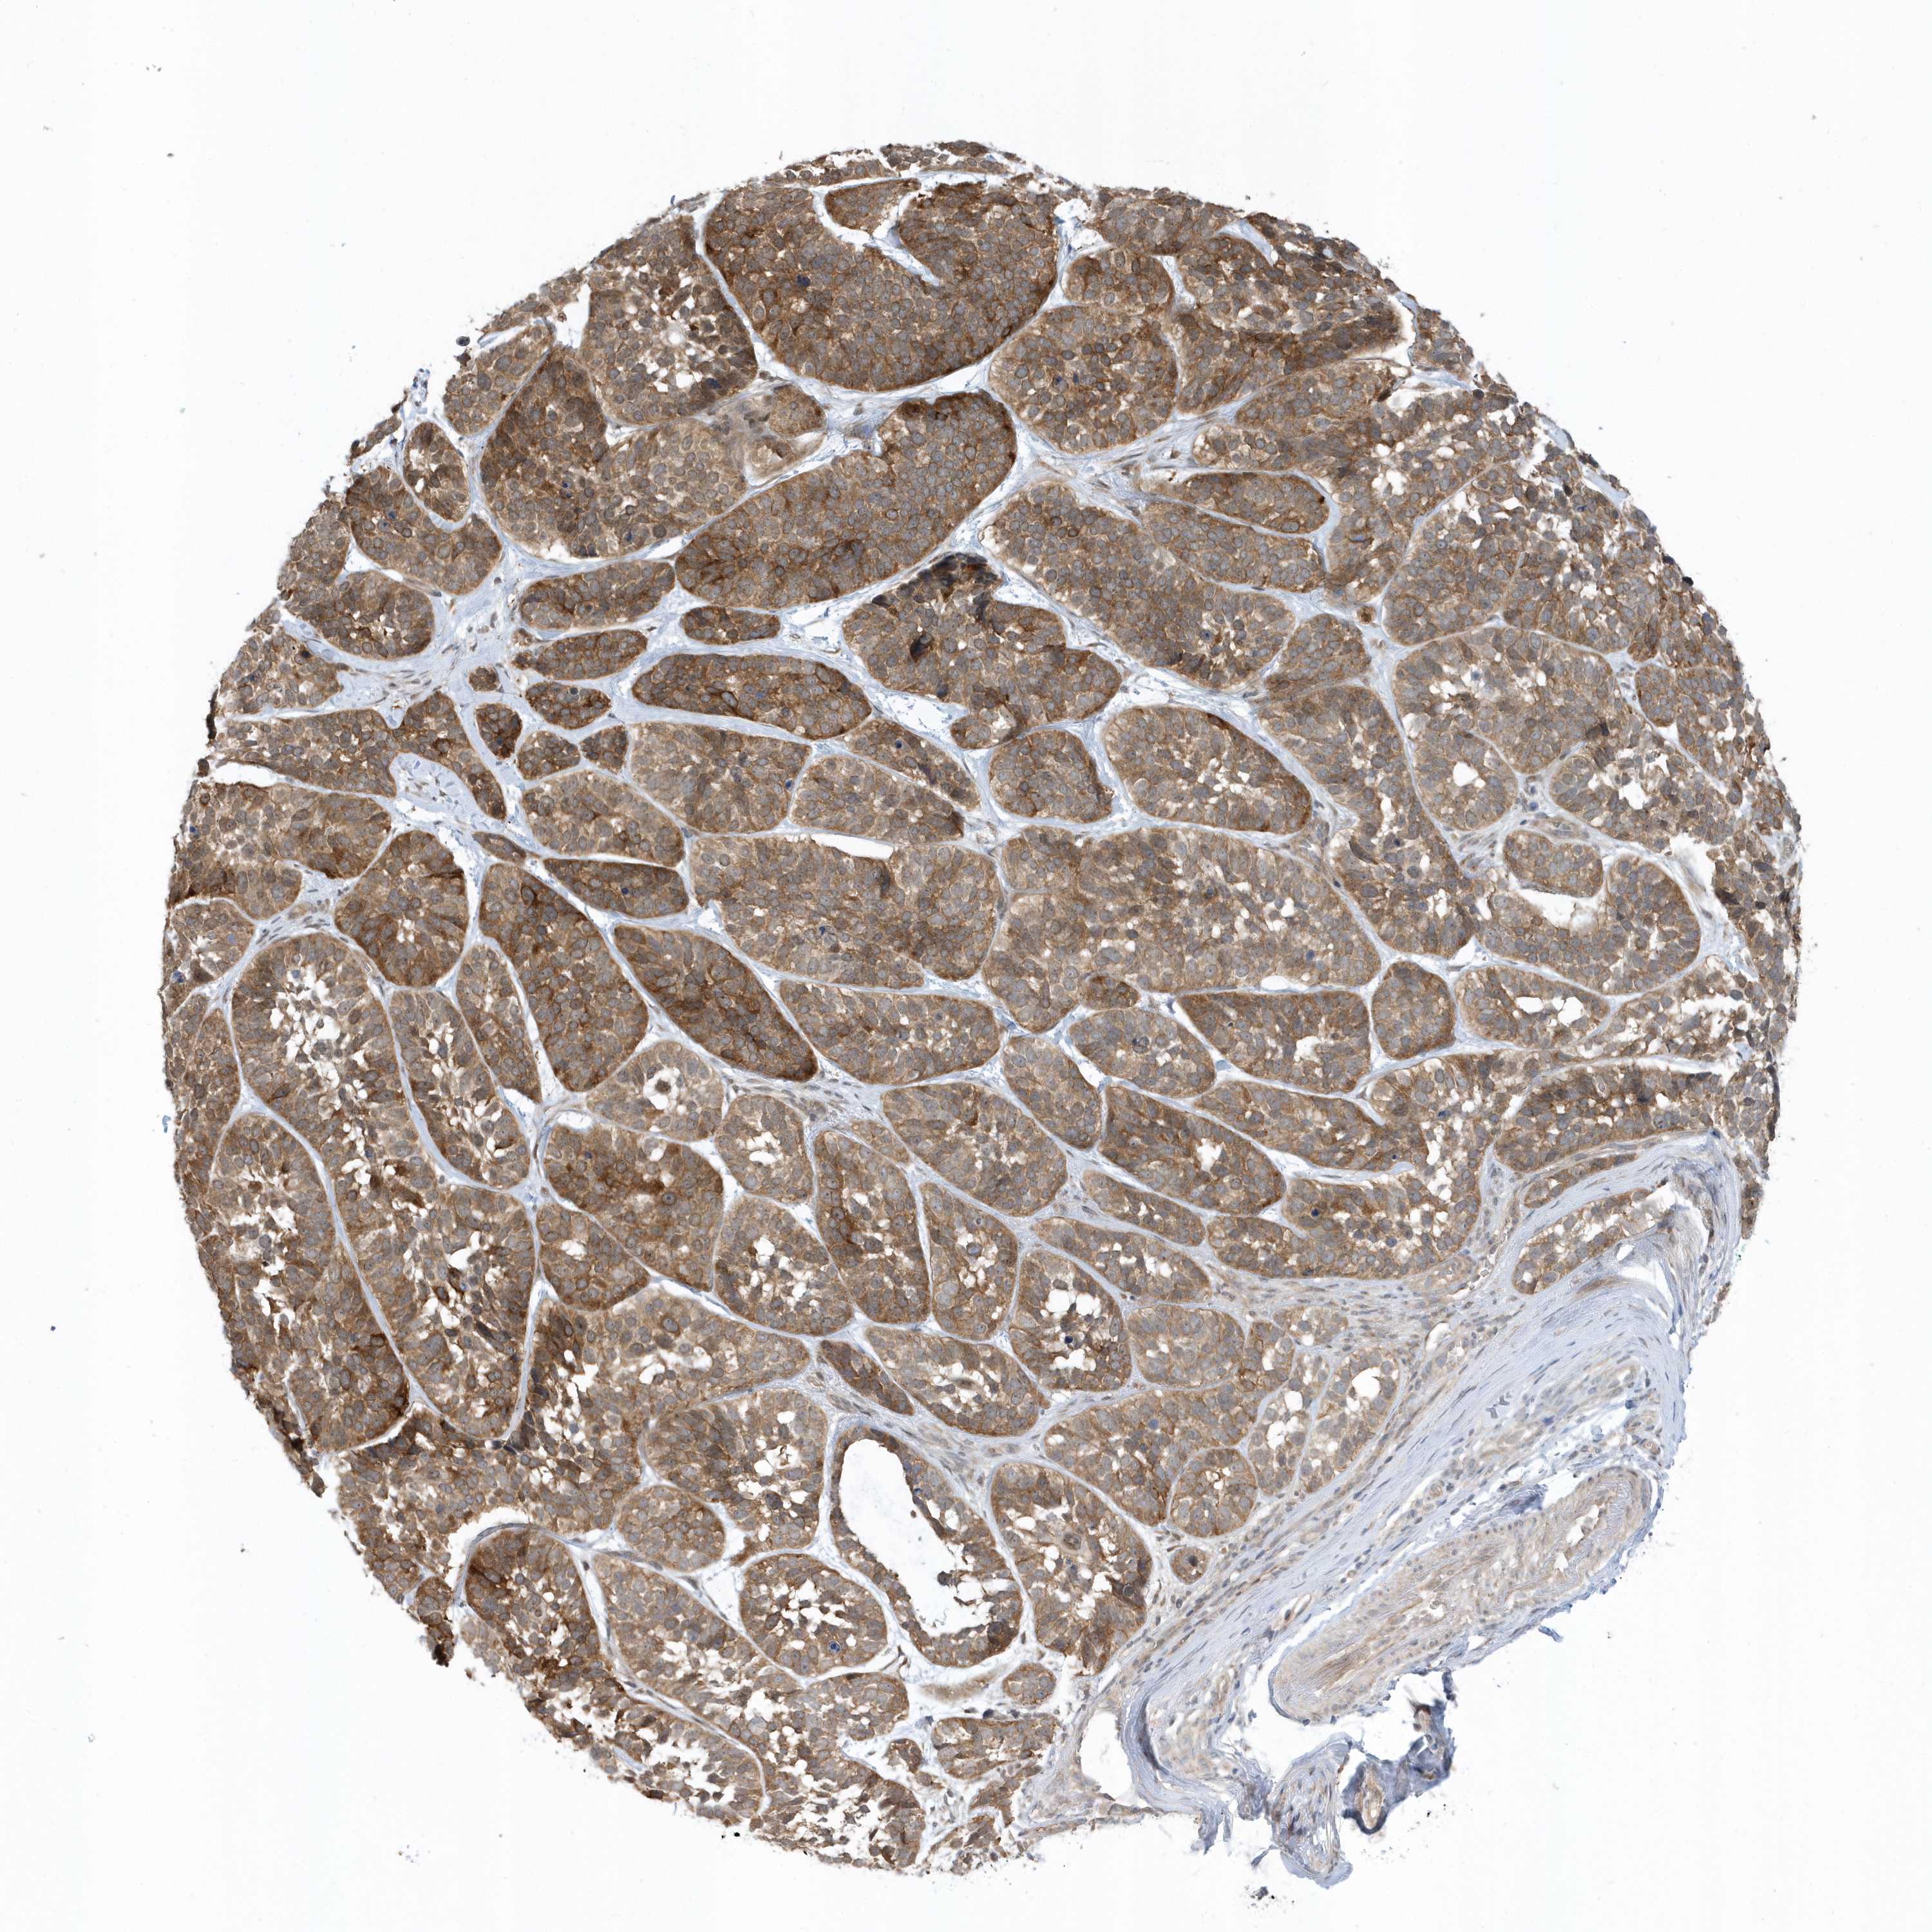

Basal cell and squamous cell cancer

SKIN CANCER - Protein expressioni

A mouse-over function shows sample information and annotation data. Click on an image to view it in a full screen mode. Samples can be filtered based on level of antibody staining by selecting one or several of the following categories: high, medium, low and not detected. The assay and annotation is described here.

Each image is clickable and will lead to virtual microscopy that enables deeper exploration of all samples and also displays staining intensity scores, fraction scores and subcellular localization as well as patient and tissue information for each sample.

Antibody HPA035844

Antibody HPA035845

Squamous cell carcinoma, NOS